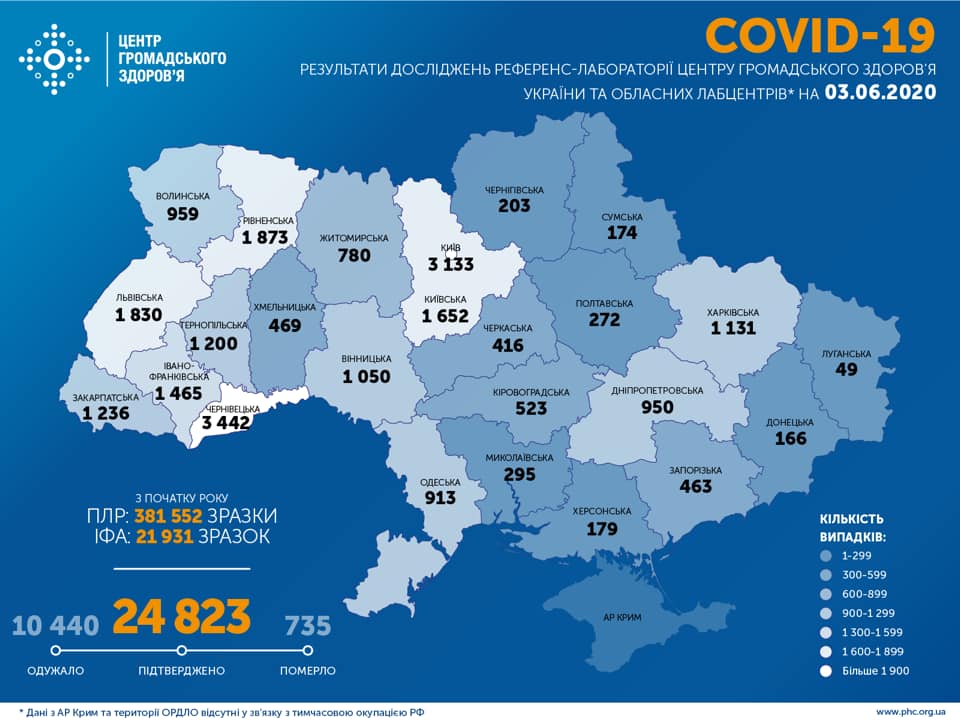

МОЗ: Уперше з початку пандемії було зроблено понад 100 тисяч ПЛР-досліджень за добу

Пів тисячі - у важкому стані, 9 жителів Рівненщини померли за добу від коронавірусу

Більше 3 тисяч випадків захворювання на коронавірус зафіксували в Україні за добу

COVID-19 на Рівненщині: 32 нових випадки, серед них 4 дітей, ще одна людина померла